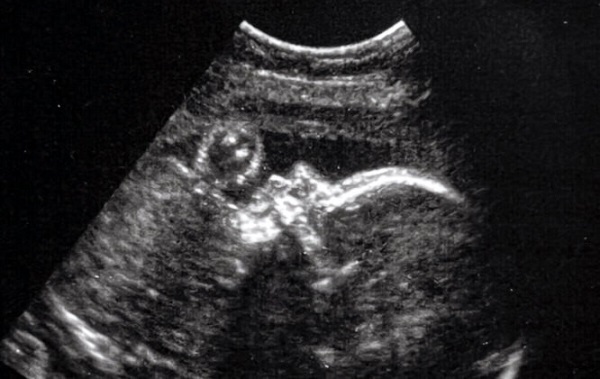

Boston Çocuk Hastanesi’ndeki bir cerrah ekibi de embolizasyona yöneldi, ancak ameliyatı sadece 34 haftalık hamileyken rahimde gerçekleştirdi. Oryantasyon için ultrason kullanıldı.